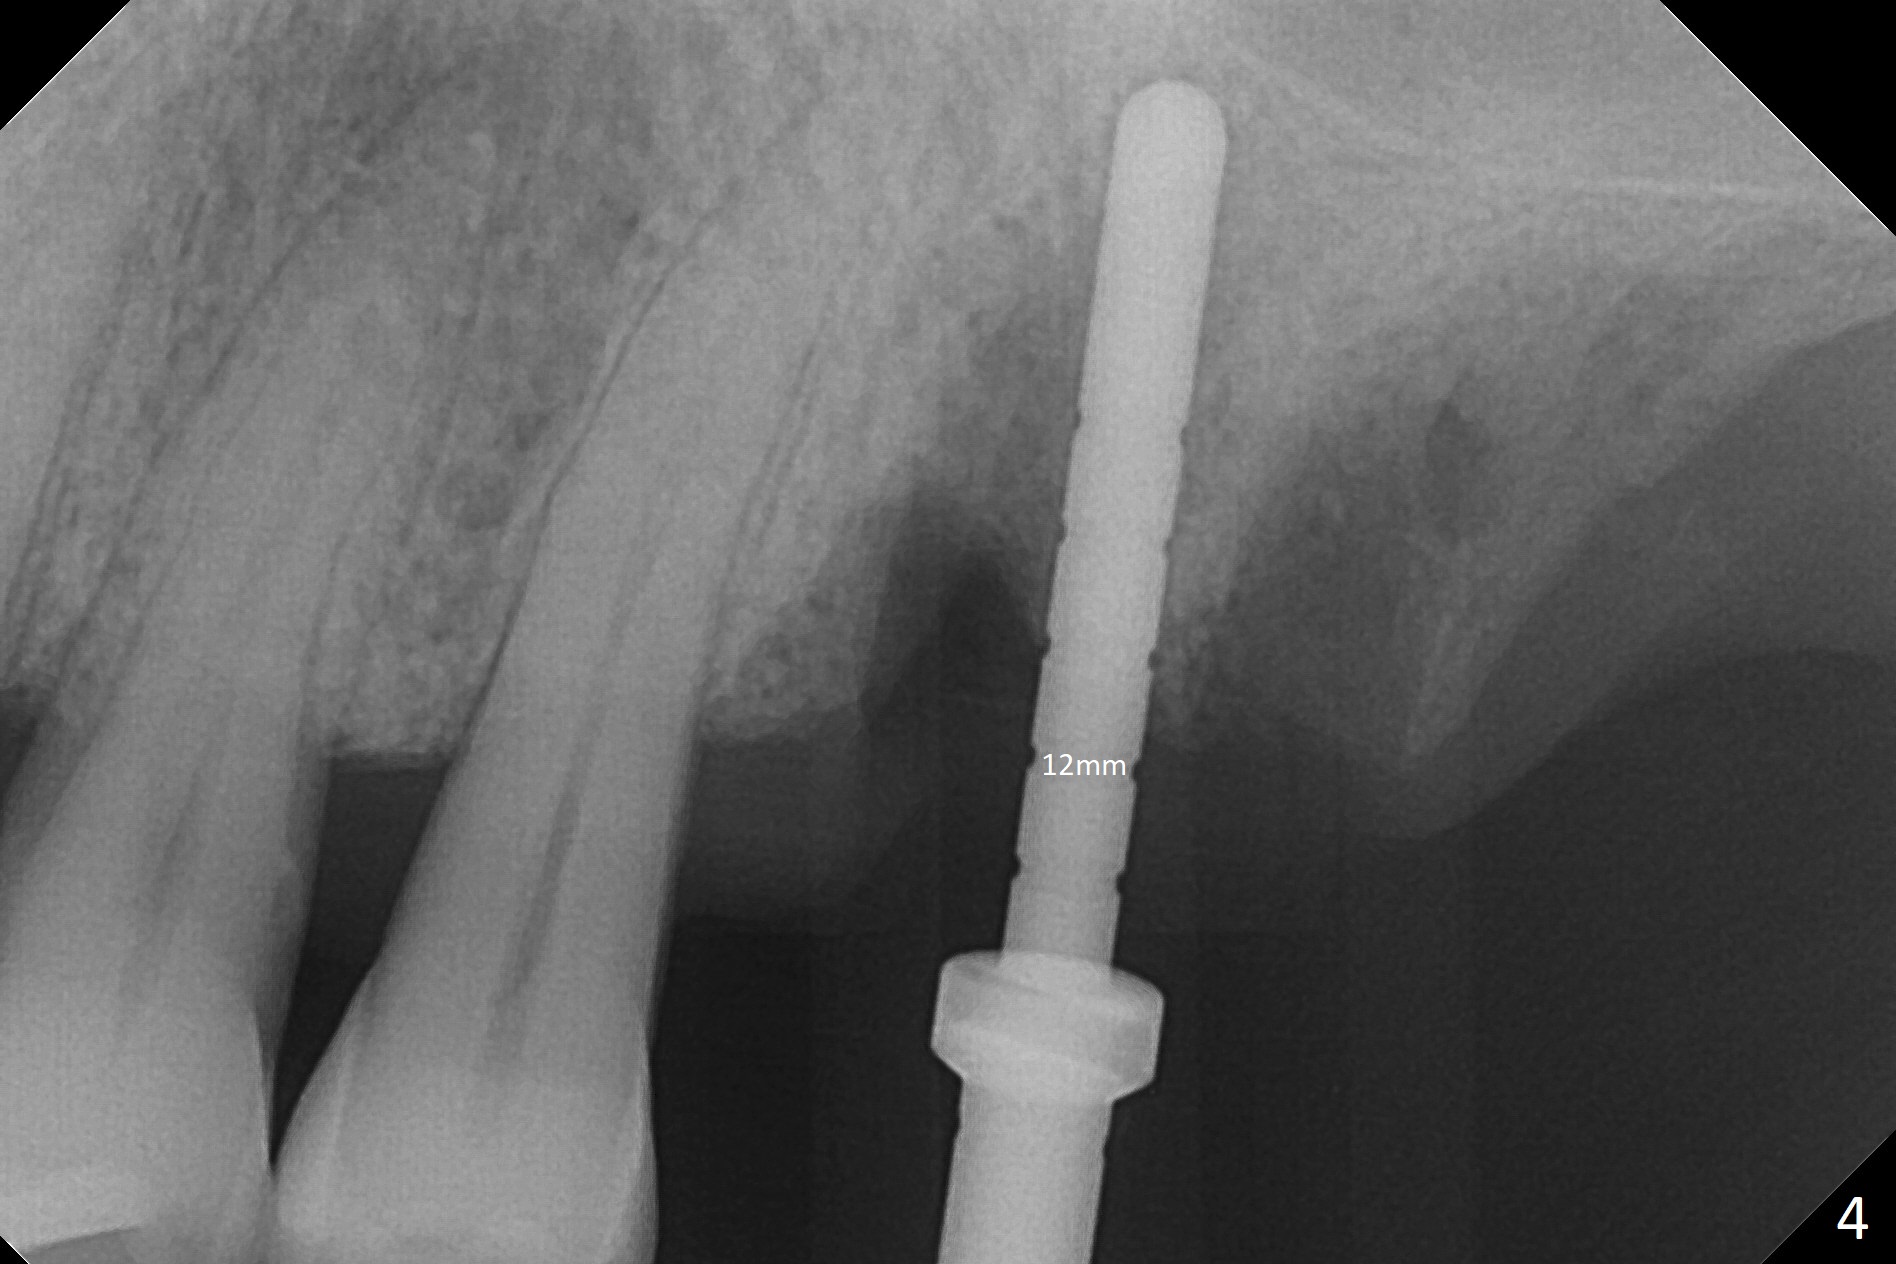

Buccal gingival recession at #14 (Fig.1) is less severe than the palatal one (Fig.2).  Without raising the buccal gingiva (Fig.3 B), osteotomy in the septum is established apparently in the middle socket (Fig.3 *, 4).  As the osteotomy increases with 3.8 mm drill, the palatal wall of the osteotomy starts to be perforating.  When a 4.5x11.5 mm implant is placed, palatal threads are exposed, to which autogenous bone and Vera Graft are placed (Fig.5 *).  After placement of a 5.5x5(3) mm abutment, an immediate provisional (Fig.6 P) is fabricated to cover the sockets.  If the septal dimension were studied carefully by raising the buccal gingiva slightly, the osteotomy could be initially more buccal so that the palatal thread exposure could be less.  When the provisional is removed 1.5 months postop, the implant is exposed palatally.  The margin of the provisional is modified so that the implant can be cleaned by the patient using Water Pik.  In fact, the healthy gingiva seems to be attached to the implant threads 2 weeks later (Fig.7).  The distal implant threads remains exposed 6 months postop; it appears that the distal socket wall has resorbed (Fig.8).  The sockets heal 1 year 7 months post cementation (Fig.9).